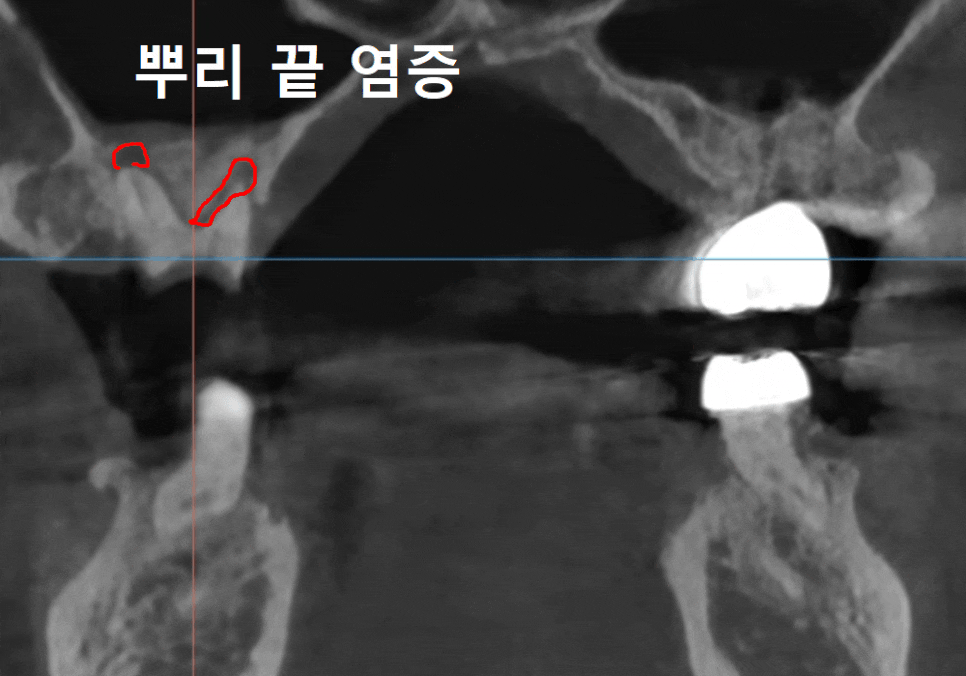

설상가상으로 뿌리 끝에는

거뭇한 염증 주머니까지 잡혀 있었죠.

240812

하지만 천만다행인 점은,

첫 번째 사례처럼 구멍을 통해

음식물 찌꺼기가 직접적으로

유입되는 최악의 상황은 아니었다는 사실!

덕분에 치아 내부가

힘없이 바스러질 정도로

심각하게 손상되지는 않았고,

뿌리 쪽 뼈 상태도 염증 없이

깨끗하게 유지될 수 있었습니다.